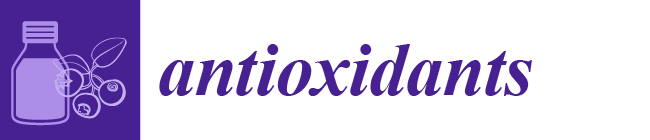

3.1. NGS-Based Genetic Screening for CCM Disease

3.3. The KRIT1 c.1664C>T Variant Leads to Aberrant Exon Skipping and Segregates with CCM Disease

3.5. Characterization of the NOTCH3 c.2960G>C Variant Identified in Case #1